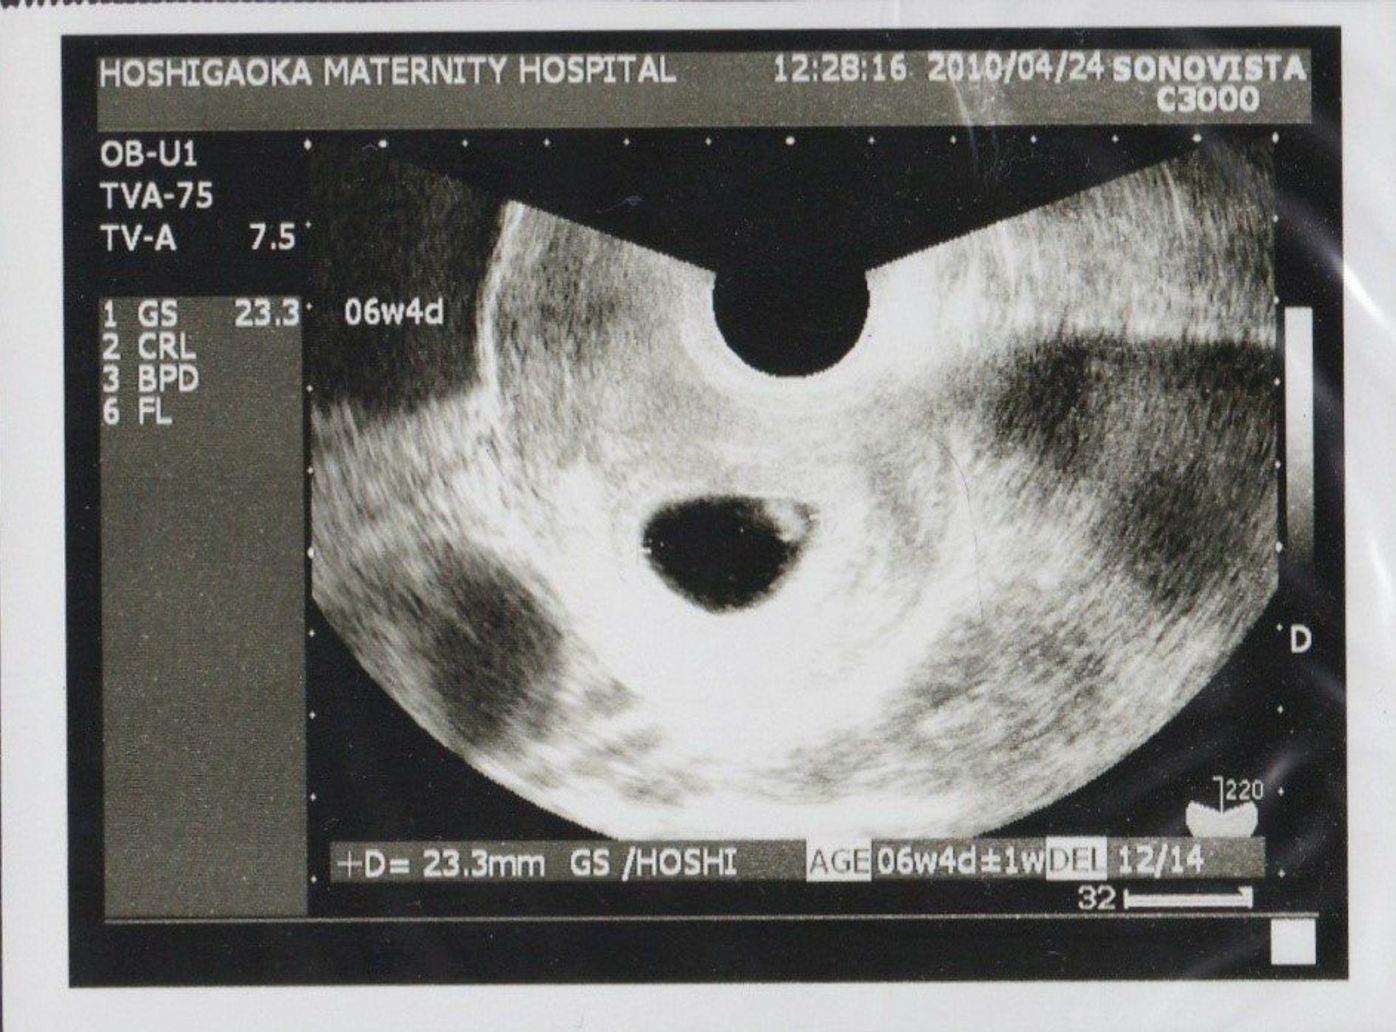

胎嚢 大きさ 平均 表-胎嚢の大きさ・頭殿長の大きさ 胎嚢の大きさと妊娠数週は以下のとおりです。 胎嚢の大きさ・頭殿長の大きさの平均値がわかります。 最大胎嚢径(GS) 頭殿長(CRL) cm 平均 範囲 cm 平均 範囲 10 4w5d 4w2d5w2d 10 7w4d 7w1d8w1d 11 4w6d 4w3d5w3d 11 7w5d 7w2d8w2d 妊娠週数ごとの胎児と母親の状態の目安一覧表 公開日: 不妊治療の種類と成功率、健康保険適用内の療法とは? 公開日: 「子宮内膜症性卵巣嚢胞(チョコレート嚢胞)」とは?癌化する確率は? 公開日:

最大胎嚢径(GS) 頭殿長(CRL) cm 平均 範囲 cm 平均 範囲 10 4w5d 4w2d5w2d 10 7w4d 7w 5週0日 胎嚢 大きさ 胎嚢(たいのう)の大きさの平均は?妊娠5週・6週・7週の目安 胎嚢は妊娠5週0日(受精後21日)までは1日に09mm、1週間で約7mmとほぼ一定の割合で成長していきます。妊娠検査薬で陽性反応が出たらまずは産婦人科を受診するでしょう。 しかしそこで「胎嚢が見えない」「胎嚢が小さい」なんてことを言われて一気に不安になってしまった。 よくあることではありますが、とても心配になってしまいますね。 今回はそんな胎嚢について、詳しくまとめてみ 今日、病院で内診をしたところ、「5w1dで胎嚢の大きさが68mmです」と言われました。以前、2度の流産を経験しており、その時は5w2d 胎嚢58mm6w2d 胎芽31mm7w1d 胎芽42mmで小さいと言われ、7w5dで心拍が停止しました。大体、5w1d

胎嚢・胎児・胎芽の平均表 昨日もまた赤ちゃん小さいんじゃないかな? ! とか思い始めちゃって沢山ググってました (コラ) そしたら! こんな表を発見! ! すぐ不安になってしまうのでこれを見て落ち着ける様に貼っておきます。 ここ。5週0日にエコーにて胎嚢が見えました。 エコー写真を2枚貰ったのですが、1枚目の大きさが55ミリ 2枚目が少し拡大された画像で41ミリと記載がありました。 5週0日でこの大きさは小さいですか? 流産してしまう確率は高いのでしょうか。 5週0日だと平均6 5週 胎嚢 大きさ 平均 5週 胎嚢 大きさ 平均<妊娠週数と胎嚢の大きさ>受精後の日数妊娠週数胎嚢(GS)の大きさ受精後16日目妊娠4週2日約15mm受精後17日目妊娠4週3日約24mm受精後18日目妊 5週までの胎嚢大きさ平均 そらの世界ひなの家〜不育症からの高齢出産!

初期流産の予測 医局カンファレンスです。 体外受精での妊娠において、胎嚢の大きさ (mGSD)と胎芽の頭臀長 (CRL)の差で初期流産を予測できるかもしれないという論文が出ていたので紹介します。 (Fertility and Sterility Vol109,No1,Jan 18) 05年から14年までの胎嚢のサイズについて教えてください! (759) 日時:12年11月08日 (木) 09時39分 名前:ベイビーライオン管理人 カズミ いつも幣サイトを見て下さってありがとうございます。本日はみなさまのお力をぜひ!頂戴したくスレッドを立てさせていただきました。